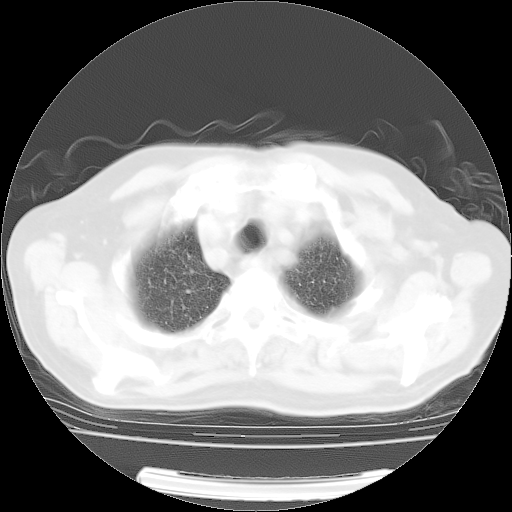

4月14日肺部CT

23.JPG

24.JPG

25.JPG

26.JPG

肺部CT平扫未见异常。